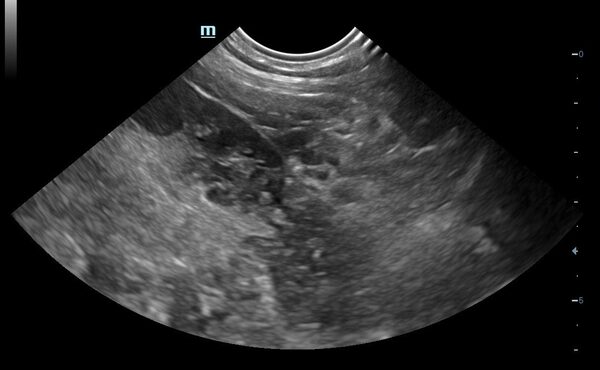

Im Ultraschall zeigten sich beide Nebennieren sehr klein:

Eine Ultraschalluntersuchung zeigte eine große Masse im Bauchraum, die bereits andere Organe verdrängte.

Magnum, ein fast 14 jähriger kastrierter Waldkatzenmix wurde uns vorgestellt, da er unter Inappetenz, Durchfall und Gewichtsverlust litt. MIttels Bildgebung (Ultraschall des Bauchraums) diagnostizierten wir einen Dünndarmtumor.

Zum Glück taten die Besitzer es nicht einfach ab und stellten ihn vor. Da der Urin stark blutig war, führten wir weiterführende Untersuchungen durch, um die Ursache zu klären. Im Ultraschall zeigten sich große Blutansammlungen und eine Urinuntersuchung ergab keinen Hinweis auf eine Infektion.